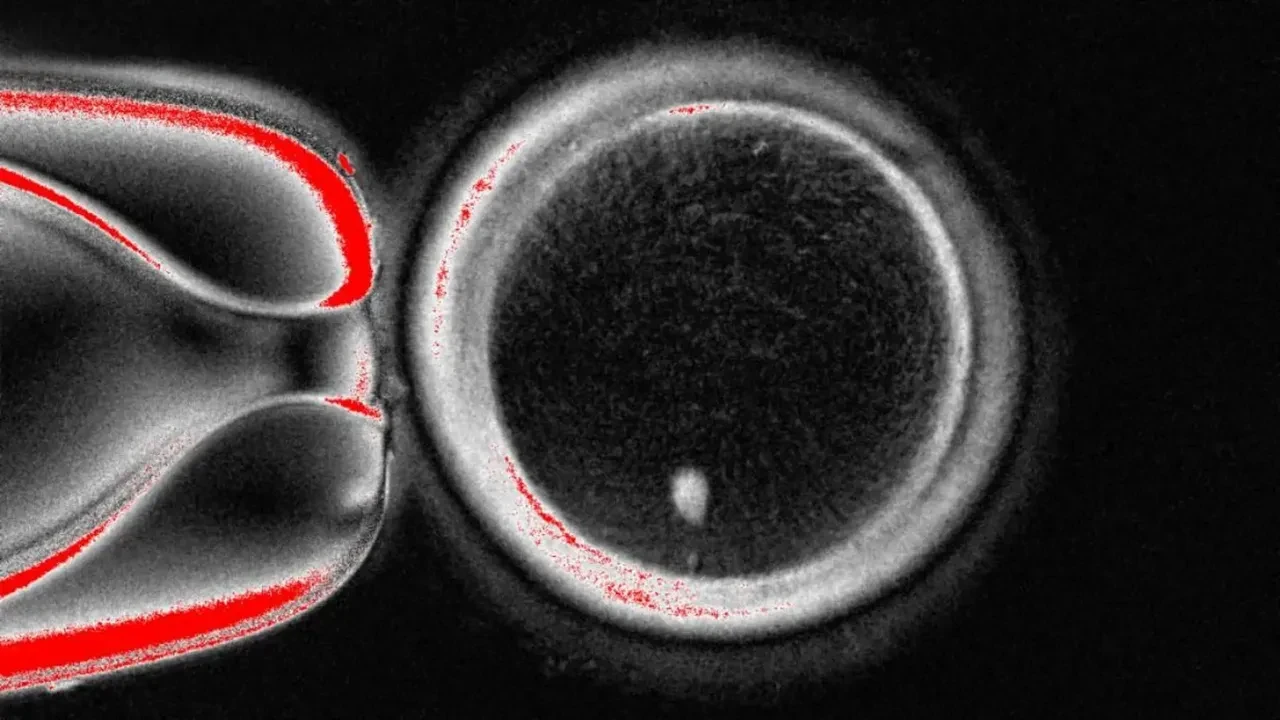

Uzmanlar, yumurta hücrelerini oluşturmak için önce normal deri hücrelerinden çekirdeği çıkardılar ve çekirdeği çıkarılmış bir donör yumurtasına aktardılar.

"Somatik hücre transferi" adı verilen işlem, 1996 yılında Dolly adlı koyunun klonlanmasında da kullanılan yöntemdi. Ancak ortada aşılması gereken bir sorun vardı: cilt hücreleri 46 kromozoma sahipken yumurtalarda 23 kromozom mevcut. Bilim insanları, hücrelerin normal bölünme şeklini taklit eden ve "mitomeiyoz" adını verdikleri bir süreçle fazla kromozomları kaldırmayı başardı.

Ekip "oosit" adı verilen 82 adet gelişmekte olan yumurta oluşturdu ve bunları tüp bebek (IVF) yöntemi ile spermle döllediler. Altı günün sonunda embriyoların yüzde 9'dan daha azının, standart bir IVF prosedürü için rahme transfer edilebilecek aşamaya geldiği bildirildi. Ancak embriyolarda çeşitli anormallikler gözlemlendikten sonra deneyin sonlandırıldığı aktarıldı.